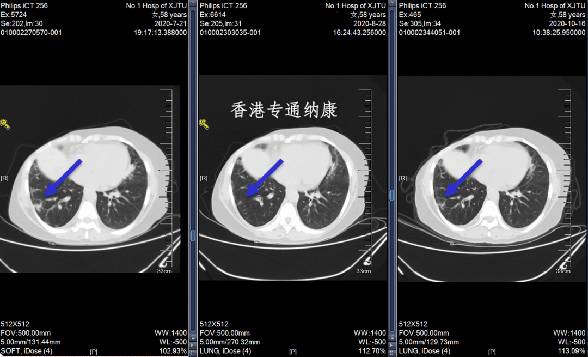

2、非小细胞肺癌

整体缓解率:54.9%~61.9%

中位无进展生存期:8.2~14个月

2022年4月20日,DS8201(中文名:德喜曲妥珠单抗)的补充生物制剂许可申请(sBLA)获FDA受理,用于治疗具有HER2突变的、不可切除或转移性非小细胞肺癌(NSCLC)患者,并被授予优先审评资格,最快将于今年第三季度获批。我们期待这款“战神”级药物的第三大适应症尽快获批,造福全球肺癌患者!